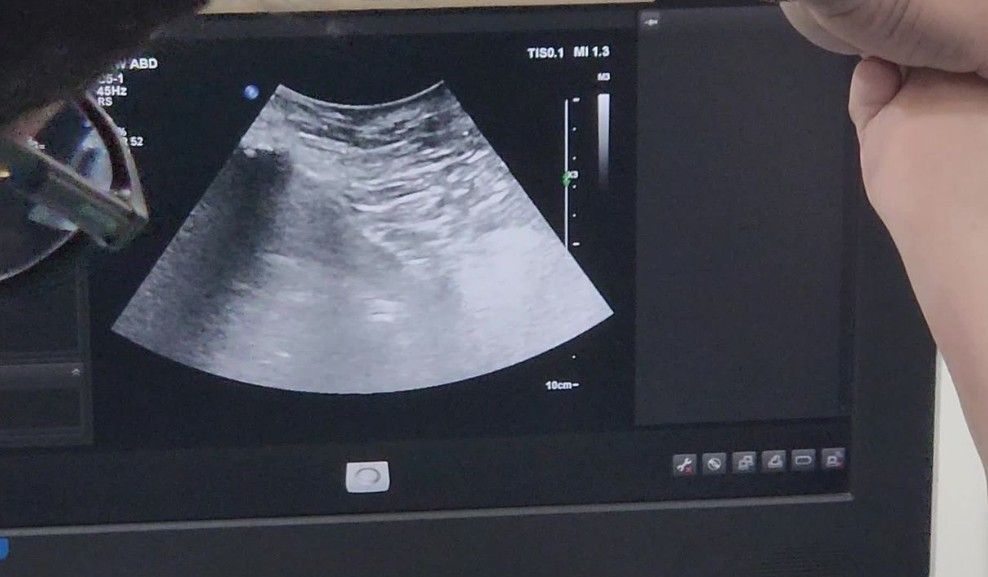

- Transperineal and transrectal ultrasound for detailed prostate imaging.

- A high-end ultrasound machine with uninterrupted power supply and a microwave Ablation machine are prepared and checked for functionality.

- Using perineal ultrasound guidance, a microwave probe is inserted into the prostate.

- White "fumes" observed on the ultrasound confirm successful tissue ablation.

- A transrectal ultrasound using a trus probe ensures the ablated areas are accurately targeted.